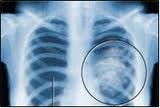

Кровотечение легочное

Легочное кровотечение представляет собой излияние крови в просвет бронхов. Эта кровь (чистая ибо смешанная с мокротой) затем выделяется вместе с мокротой.

Причинами этого кровотечения могут стать: деструктивные формы заболеваний, туберкулезы гангрена абсцесс. Распадающийся рак легких. При туберкулезе кровотечения осложняют казеозную пневмонию, инфильтративные формы, фиброзные процессы. Читать далее